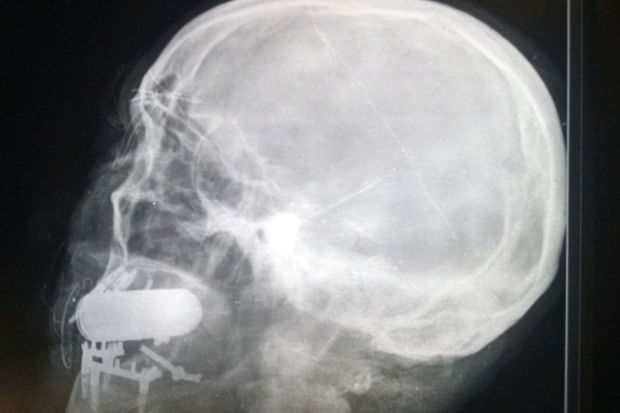

Müdaxilədən əvvəl döyüşçü rentgen müayinəsindən keçib. Görüntüdə mütəxəssislər yad cisim aşkar ediblər, lakin onun mənşəyi məlum olmayıb. Əşyanın döyüş sursatı olduğu təxmin edilir. Təhlükəsizlik üçün cərrah gülləkeçirməz jilet, taktiki eynək və dəbilqə taxıb.